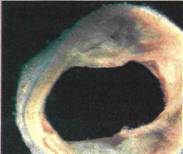

Τμήμα της αορτής του ανθρώπου με εναποθέσεις λιπαρών και άλλων ουσιών στα τοιχώματά της.

εικόνα

στα τοιχώματα των αγγείων περιορίζει τη διατομή τους (αρτηριοσκλήρυνση). Αυτό έχει ως αποτέλεσμα να ελαττώνεται ή και να διακόπτεται τελείως η ροή του αίματος. Ανάλογα με την έκταση του φαινομένου και την περιοχή στην οποία συμβαίνει προκαλούνται πολλές ανεπιθύμητες καταστάσεις. Σε ότι αφορά τον άνθρωπο, σ' αυτές περιλαμβάνεται ο εκφυλισμός των ιστών ή και ο θάνατος τους εξαιτίας διακοπής στην παροχή αίματος, η δημιουργία θρόμβων, που μεταφερόμενοι με την κυκλοφορία του αίματος αποφράζουν τα αγγεία και η επιβάρυνση της λειτουργίας της καρδιάς, που εργάζεται εντονότερα, ώστε να στείλει σε ολόκληρο τον οργανισμό την απαραίτητη ποσότητα αίματος.

Σοβαρότερες περιπτώσεις είναι τα εγκεφαλικά επεισόδια από την απόφραξη ή τη ρήξη των αρτηριών του εγκεφάλου και τα εμφράγματα της καρδιάς από την απόφραξη των στεφανιαίων αρτηριών.